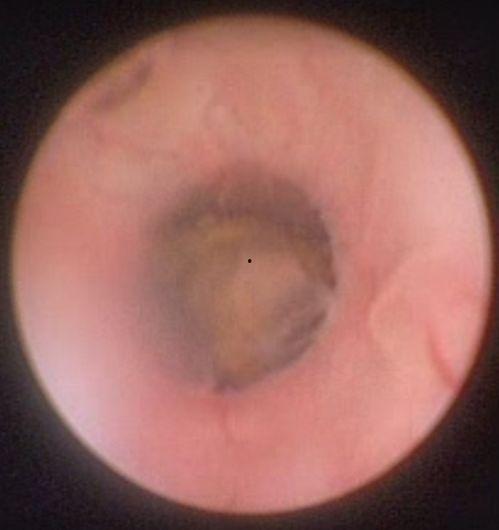

输尿管硬镜手术,顾名思义,就是使用一根硬质的镜子——输尿管硬镜,通过尿道进入膀胱,再进入输尿管,对堵塞部位进行观察和手术。听起来是不是有点像科幻电影里的场景?其实,这可不是虚构的,而是真实存在的医疗技术。

3. 输尿管硬镜进入:医生将输尿管硬镜通过尿道、膀胱,进入输尿管。

4. 观察与手术:通过输尿管硬镜,医生可以清晰地观察到堵塞部位的情况,然后进行手术,比如碎石、切除肿瘤等。

现在,让我们来看看一段输尿管硬镜手术的视频,感受一下手术的全过程。

[视频:输尿管硬镜手术全过程]

看完这段视频,是不是觉得手术过程并不复杂呢?其实,输尿管硬镜手术是一种微创手术,创伤小、恢复快,是治疗输尿管堵塞的有效方法。